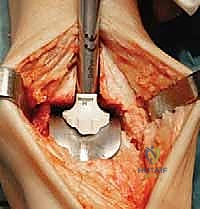

تُجرى العملية عادة تحت التخدير العام أو التخدير النصفي (الشوكي). يقوم د. هطيف بعمل شق جراحي أمامي أو جانبي (حسب التقنية المستخدمة وحالة المريض) للوصول إلى مفصل الكاحل بعناية، مع الحفاظ على الأوتار والأعصاب والأوعية الدموية المحيطة.

3. إزالة الأسطح التالفة (تحضير العظام)

باستخدام أدوات جراحية دقيقة وموجهات خاصة، يتم إزالة الغضاريف التالفة وجزء رقيق جداً من العظام المريضة من نهايتي عظمة الظنبوب وعظمة الكاحل (Talus). يتم تشكيل العظام بدقة لتتطابق تماماً مع شكل أجزاء المفصل الصناعي.